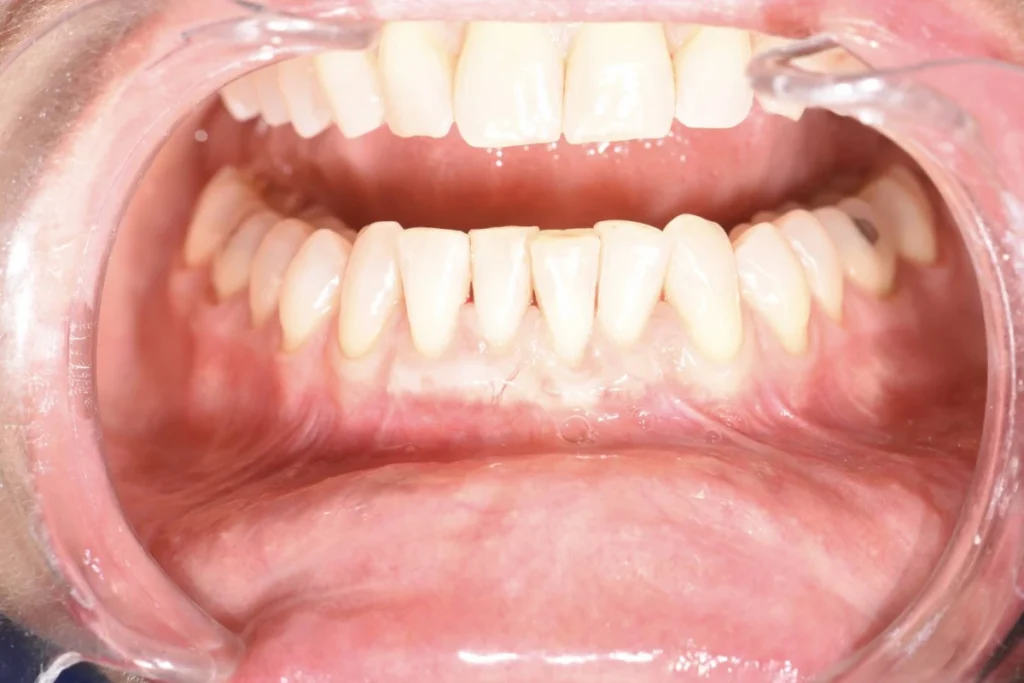

Monsieur R, 33 ans, se présente à la consultation pour améliorer l’esthétique de son sourire. Après une consultation approfondie, nous posons le diagnostic d’une « éruption passive incomplète ». Cela signifie qu’une partie des dents du patient est « cachée » par un excès de gencive. Cela donne l’impression de dents trop petites et d’une gencive trop visible lors du sourire. On appelle cela un « sourire gingival ».

Le traitement va donc consister en une intervention chirurgicale qui permettra de retirer cet excès de gencive pour rendre visible les dents dans leur intégralité. L’intervention réalisée sous anesthésie locale est totalement indolore et les suites opératoires assez limitées. Après quelques jours de cicatrisation, le résultat est déjà présent et le patient ravi d’avoir améliorer l’aspect de son sourire sans avoir touché à ses dents !